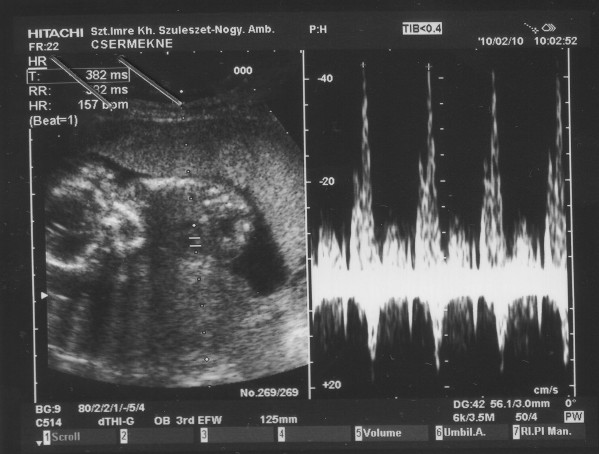

Nagyon örülök, hogy minden rendben Riccardoval